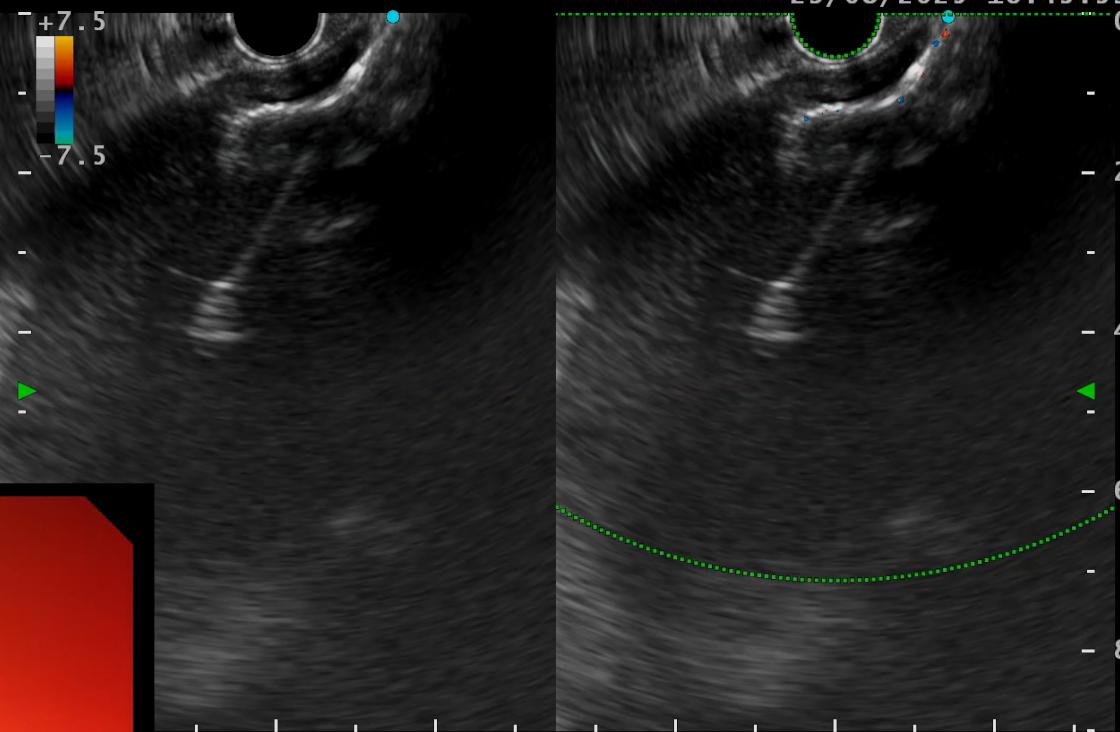

刘娟副教授在超声胃镜引导下进行囊肿穿刺

超声胃镜引导下支架释放

大量褐色浑浊囊液经支架迅速涌出